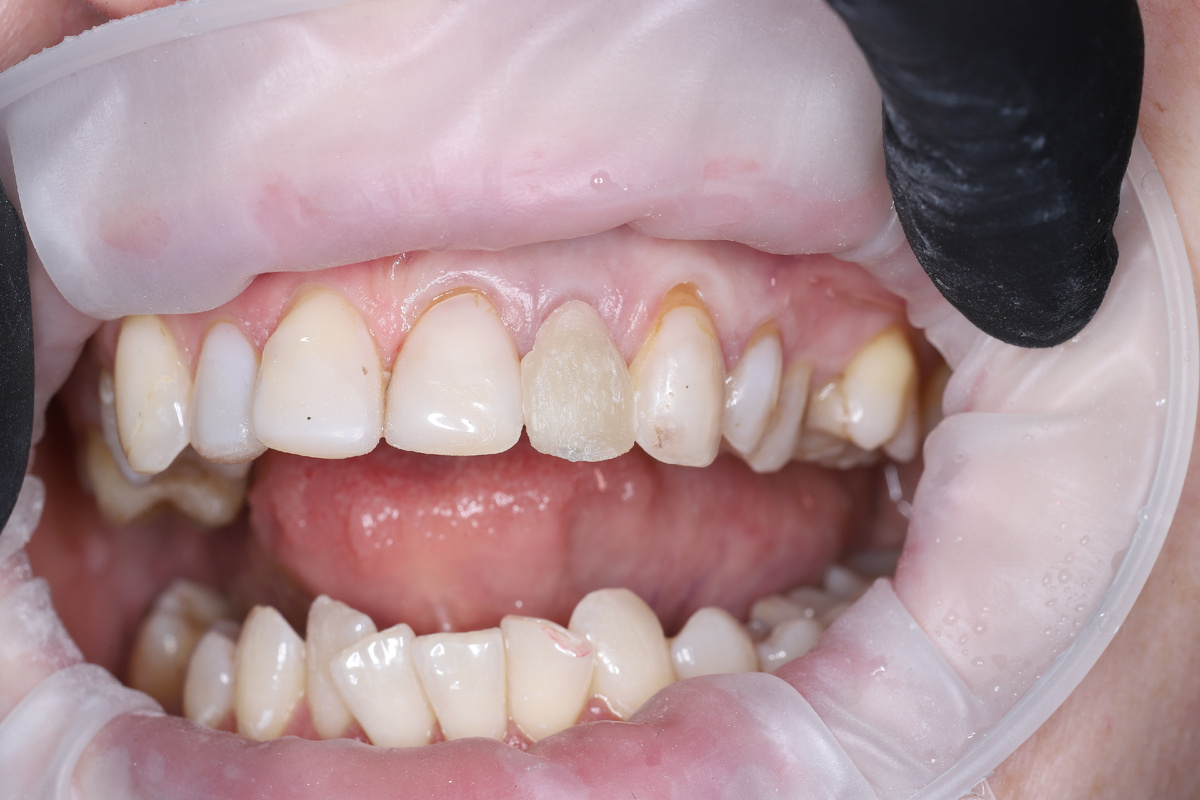

Далее удалил зуб, поставил имплант, вкрутил опорный элемент (временный абатмент) и сделал временную коронку на нём:

ситуация после установки временной коронки